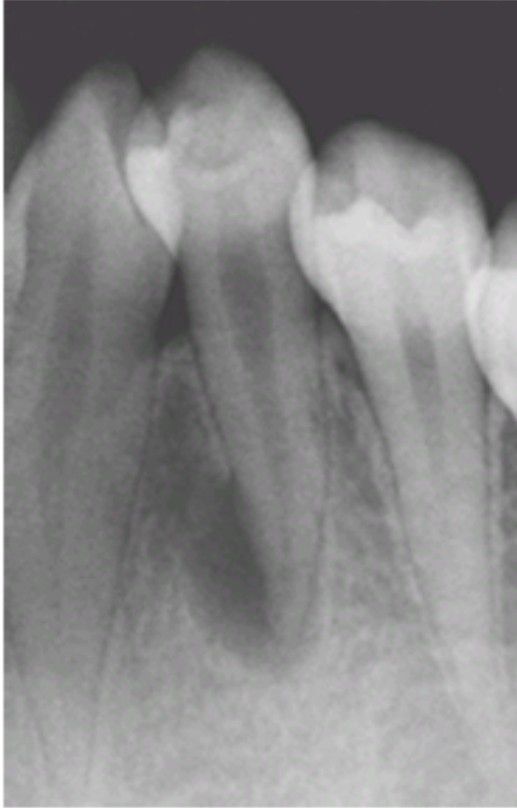

Dens evaginatus

Note the tuberculated occlusal anatomy. Attrition on the accessory cusp led to pulpal necrosis and periapical inflammatory disease.